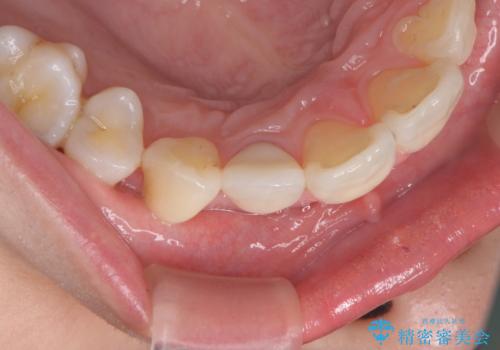

- 右上前歯の形と色が気になるとのことで来院された患者様です。

残っている歯に亀裂が多く走っていたため、クラウンでの修復処置を行います。

歯ぐきの扱いに気を付けることで、術前よりも歯ぐきの位置が改善されました。